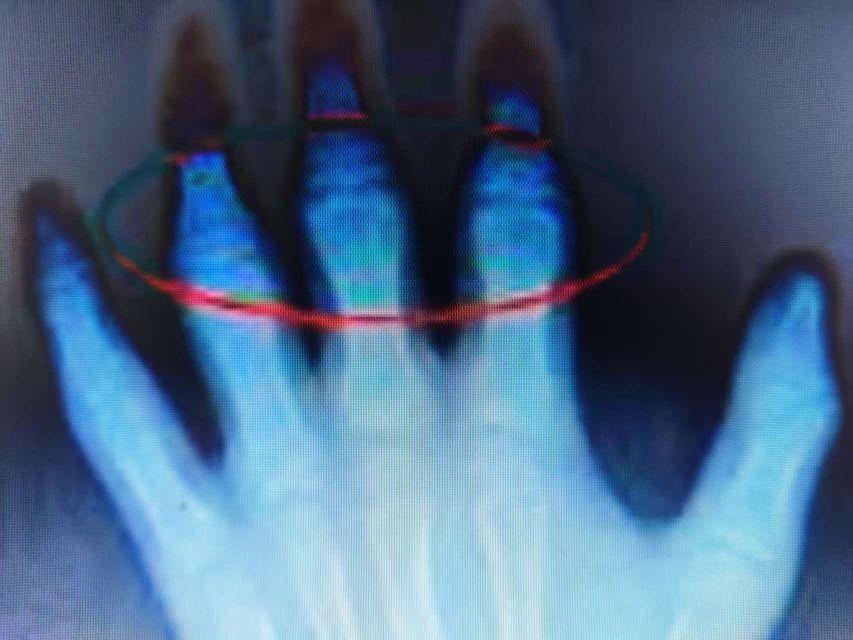

隨著骨骼發(fā)育加速,PPVD的病理改變逐漸顯現(xiàn):患兒的雙膝、髖、肘、腕等大關(guān)節(jié)出現(xiàn)對(duì)稱(chēng)性梭形腫脹(非炎癥性,實(shí)為關(guān)節(jié)周?chē)琴樑c軟骨下骨硬化),但觸之無(wú)皮溫升高或壓痛(區(qū)別于感染性或炎癥性關(guān)節(jié)炎)。關(guān)節(jié)活動(dòng)度進(jìn)行性下降——膝關(guān)節(jié)屈曲攣縮(蹲不下)、髖關(guān)節(jié)外旋受限(走路呈“鴨步”)、手指小關(guān)節(jié)僵硬(握筆或系鞋帶困難)。

X線片:早期表現(xiàn)為關(guān)節(jié)周?chē)趋颗虼螅ㄈ缦リP(guān)節(jié)的股骨髁或脛骨平臺(tái)邊緣“波浪狀”增生)、干骺端增寬(生長(zhǎng)板軟骨異常堆積);進(jìn)展期可見(jiàn)關(guān)節(jié)間隙輕度變窄(非炎癥性磨損)、軟骨下骨硬化(類(lèi)似骨關(guān)節(jié)炎,但無(wú)囊性變或骨贅的“邊緣銳利”特征);脊柱表現(xiàn)為椎體終板不規(guī)則、椎間隙均勻狹窄(無(wú)強(qiáng)直性脊柱炎的骨橋或韌帶骨化)。